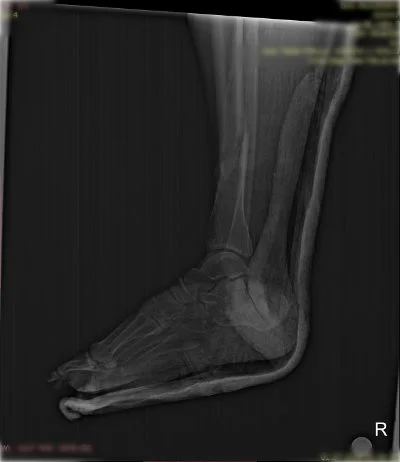

Görüntüleri büyütmek için resmin üstüne tıklayınız.